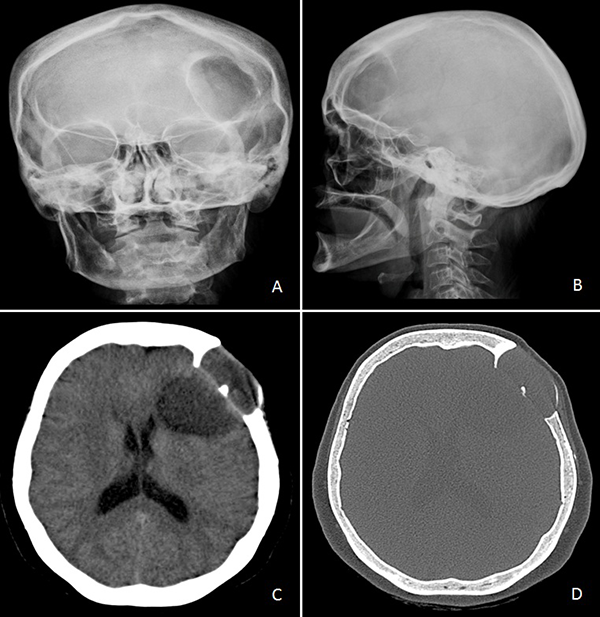

Concurrió con una radiografía (Rx) de cráneo frente y perfil donde se evidenció una lesión radiolúcida, circular y de bordes definidos con signos de remodelación esclerótica (Figura 1A y B). Tomografía computada (TC) de encéfalo mostró una lesión lítica de calota con deformación y esclerosis de la misma asociada a compromiso subgaleal, invasión intradural y extensión intraparenquimatosa en imagen de “reloj de arena” (Figura 1C y D).

Figura 1. A) y B) Rx de cráneo frente y perfil. C) y D) TC de cerebro sin contraste endovenoso.